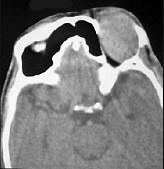

问题 男性45岁,左眼疼痛伴视力下降一个多月,左眼明显外突,CT扫描如图所示,最可能诊断为 ( )

选项 A、眶内结核 B、眶内转移瘤 C、眶内血管瘤 D、眶内纤维瘤 E、左侧眶内炎性假瘤

答案 E